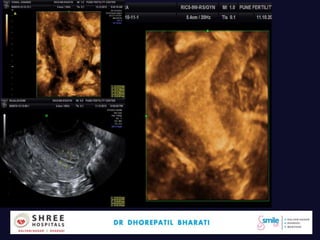

• Case C..

• Day 11…DF..19.9mm,Endo 6.5mm

• PSV 7,RI>0.45,v.poor perifollicular flow

• Timeline…LUF..